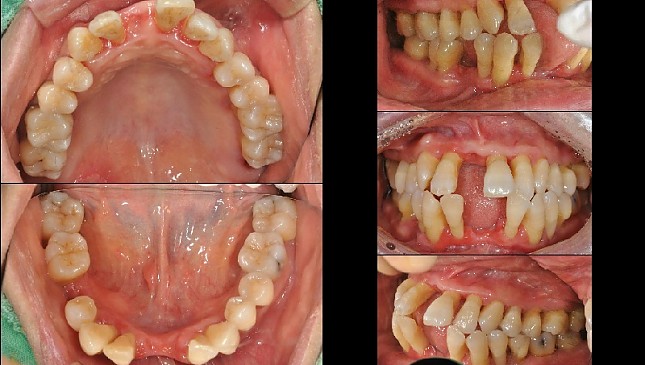

치아살리기 치료 전후 사진

잇몸재생교정 치료 전후사진

잇몸 전체가 무너져 동시다발적으로 죽어가던 치아들을 한꺼번에 살려 냅니다.